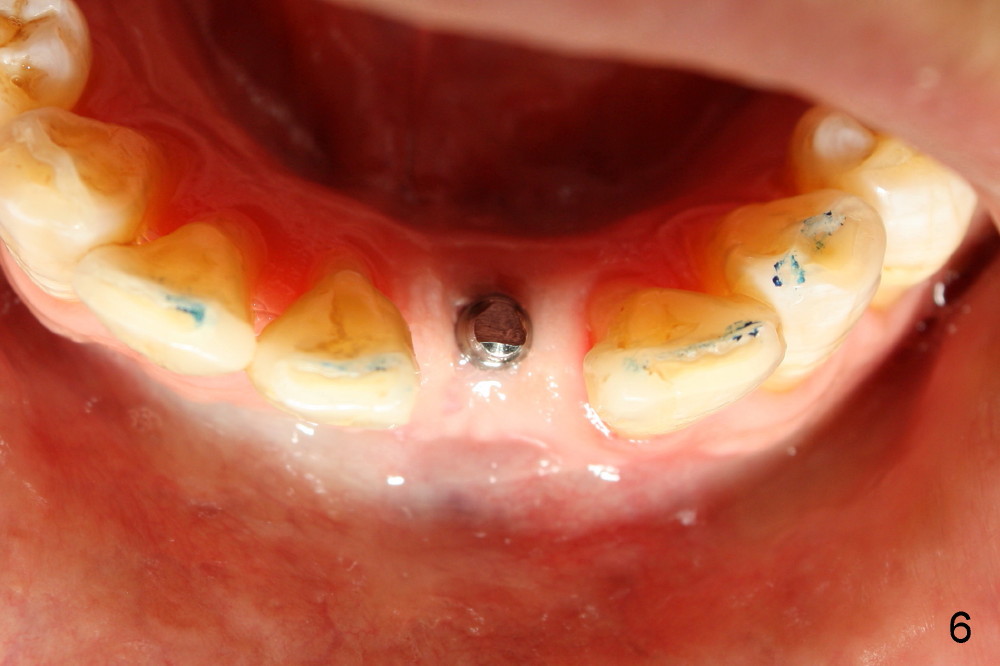

A 3x17 mm one piece implant is planned.  Osteotomy is created by a 1.5 mm pilot drill at the depth of 14 mm without incision (Fig.2); it is close to a neighboring incisor.  The trajectory of the osteotomy is intended to be changed (Fig.3 red) without success (white, 17 mm deep).  With measurement and calculation, the 3x17 mm implant is not expected to touch the root of the adjoining tooth.  In fact it is fine with insertion torque between 50-60 Ncm (Fig.4).  Without incision, the papillae appear to form immediately following implantation (Fig.5).  With adjustment of the abutment (Fig.6), an immediate provisional is fabricated (Fig.7).